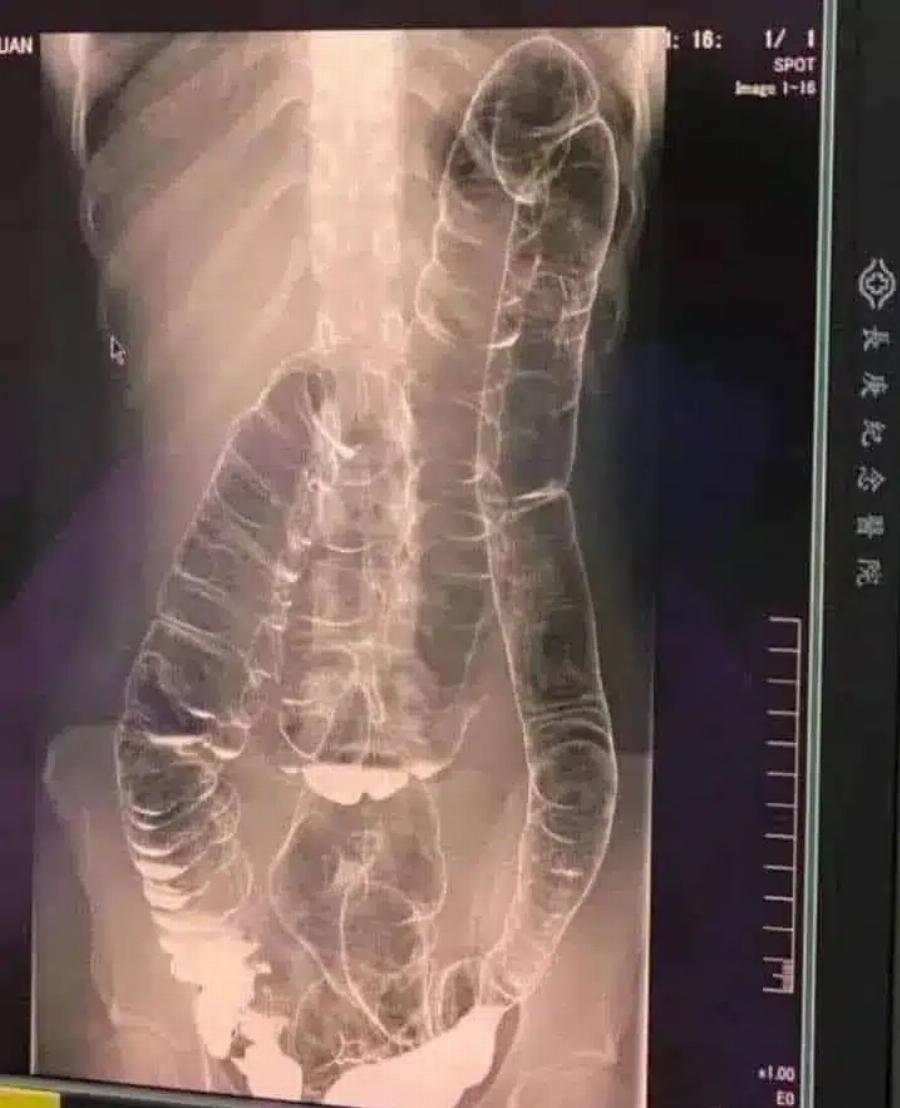

Η παρακάτω εικόνα με ακτίνες Χ ανήκει σε μια νεαρή γυναίκα που έπασχε από χρόνια δυσκοιλιότητα για χρόνια.

Μια μέρα, η κατάστασή της επιδεινώθηκε και έμεινε για πάνω από δύο εβδομάδες χωρίς κένωση.

Αναζήτησε τελικά ιατρική βοήθεια, αλλά τα αποτελέσματα ήταν ανησυχητικά.

Στην ακτινογραφία, μπορείτε να δείτε πώς το κόλον έχει επεκταθεί δραματικά, φτάνοντας μέχρι την περιοχή του θώρακα, κοντά στην καρδιά.

Οι φυσιολογικές πτυχές και διπλώσεις του παχέος εντέρου, που είναι απαραίτητες για τη λειτουργία του, έχουν σχεδόν εξαφανιστεί λόγω υπερβολικού φουσκώματος και διάτασης.